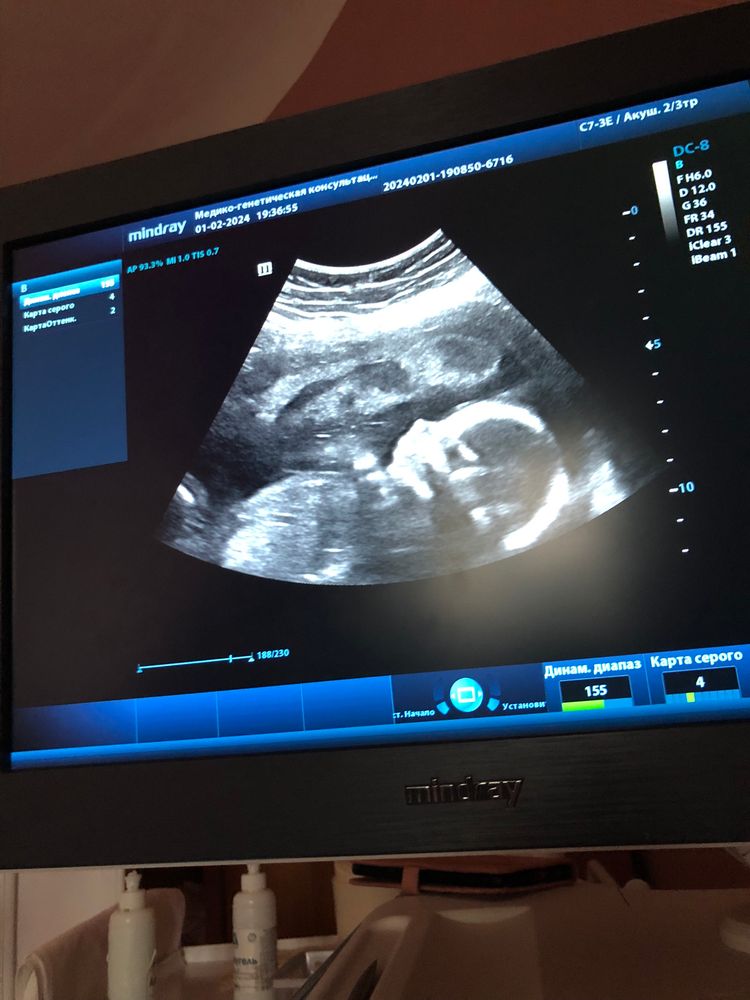

Это узи в 17 недель ,узнавала пол малыша🤭сейчас уже 31неделя.Как тут не умиляться ?Возможно не у ребенка уродство ,а у вас с головой ,без обид)Люди мечтают о детях ,а тут такой пост 😅Хотя возможно гормоны так дают о себе знать.Ну я вам так скажу ,они и рождаются ни как на картинках у блогеров 😂там сморщенные сине-фиолетовые пришельцы 🫣🤣

вот сейчас 17 недель, была на 1 скрининге, сегодня ходила на явку, всегда узи и 3д картинки. Я не понимаю как ощущать что-то приятное, мне кринжово от этих картинок, там довольно стремный плод, но, думаю, врач бы сказал, если бы увидел уродство?